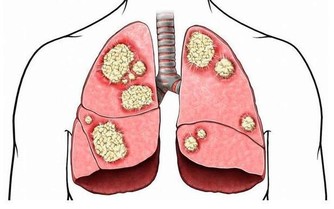

我們在積極的進行降溫措施的同時,有條件的時候,就應該積極去尋求藥物治療,一般來說感冒發燒都是因為體內炎症過重導致的,因此在選擇藥物時可以選擇消炎的中成藥。

治療上經常見到的就有解熱消炎膠囊,解熱消炎膠囊由多種抗炎藥物組成,可以鎮靜安神,清熱解毒。主治外感風熱引起的發燒,咽喉腫痛,扁桃體炎,咽炎等症。除了孕婦不能使用外,其他人群都可以在醫生的正確醫囑下使用該藥物。